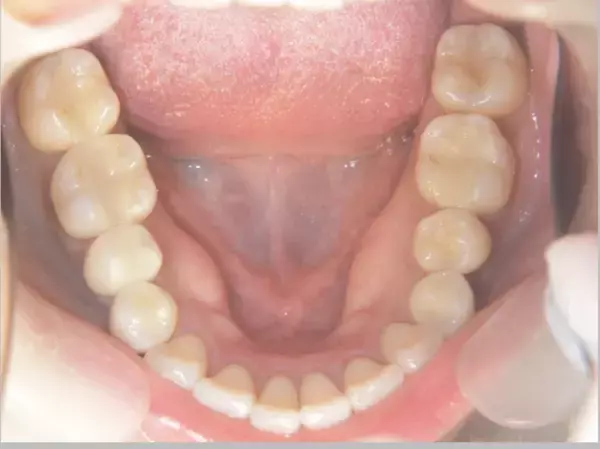

睡眠中の歯ぎしりや食いしばりは自覚しにくいことが特徴です。長期間にわたり口腔内に力が加わることで、顎の骨がその負荷に適応し、「骨隆起(こつりゅうき)」と呼ばれる骨のふくらみが形成されることがあります。

骨隆起は下顎の内側(舌の付け根付近)や上顎中央部に見られ、自覚症状がないまま進行するケースも少なくありません。

舌で触れた際に「内側に硬い出っ張りがある」と感じる方は、一度確認のきっかけになる場合があります。「自分には関係ない」と思っている方でも、実際に確認すると見られるケースは少なくありません。

当院の臨床では、20代後半の患者においても骨隆起が確認される例があり、無意識の咬合圧が比較的若い年代から蓄積している可能性も考えられます。

画像 : https://newscast.jp/attachments/qDF9B9OSnSZS3xLKfQqn.jpeg